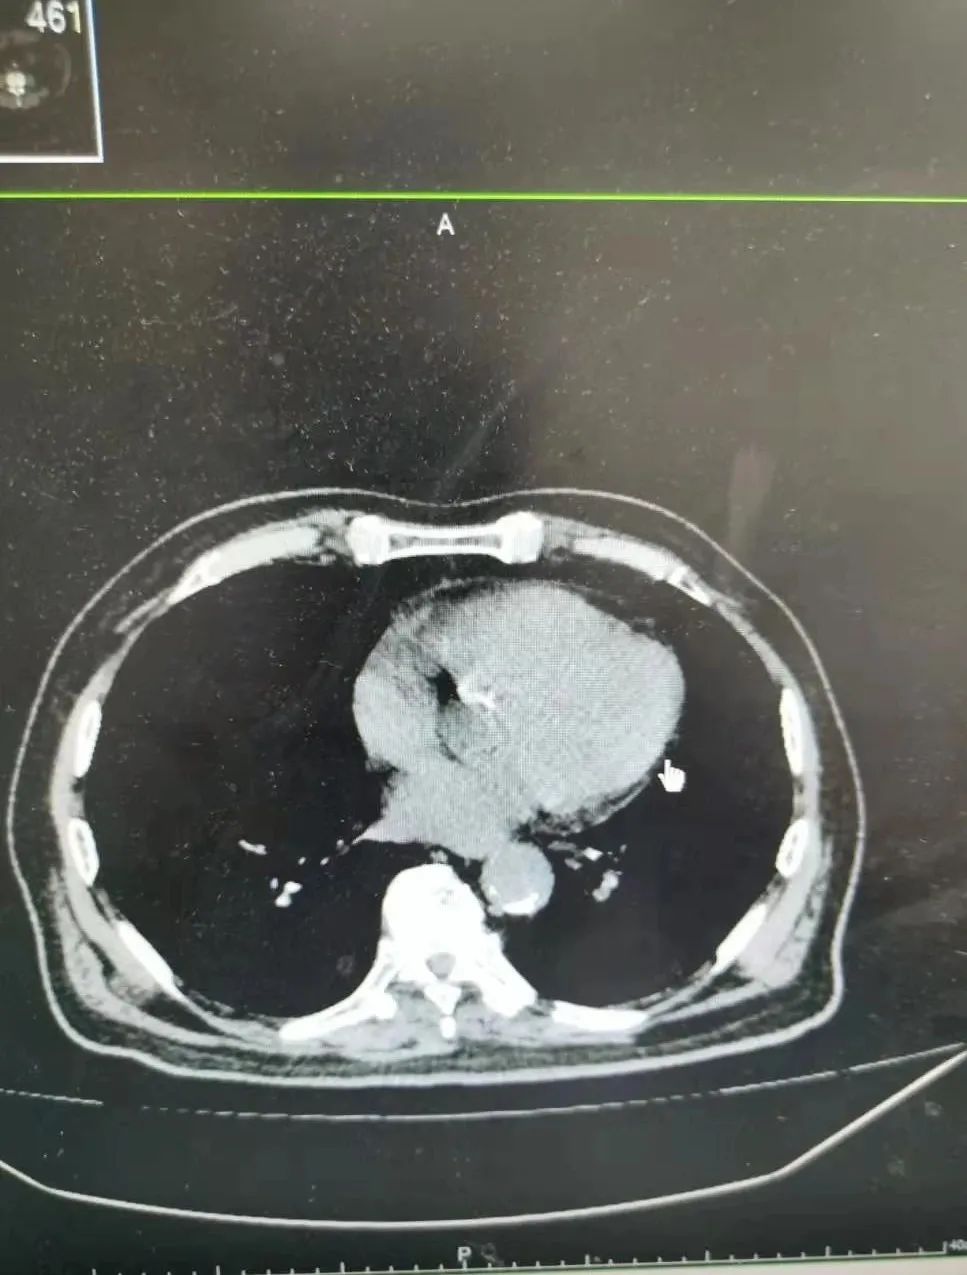

91 岁的吴老先生是高校退休教师,半个多月前他在家人陪同下去医院看诊。吴老告诉医生,自己间断便血已经 1 个多月了。检查确诊为直肠癌,肿块位置极低,距离肛门仅 4 公分。

而且,老人患有糖尿病、阻塞性肺气肿、低蛋白血症、心动过速等多种慢性病,心肺功能极差。姚磊请来心血管内科、呼吸内科、内分泌科、麻醉科等专家综合评估后,决定为吴老先生实施全腹腔镜下极限保肛手术。

棘手的是,吴老先生有近 180 斤体重,BMI 指数达到 28。男性本来骨盆就窄,腹腔镜下手术视野受限,肥胖更是增加了手术难度。在手术室麻醉科的全力支持下,手术最终顺利完成。